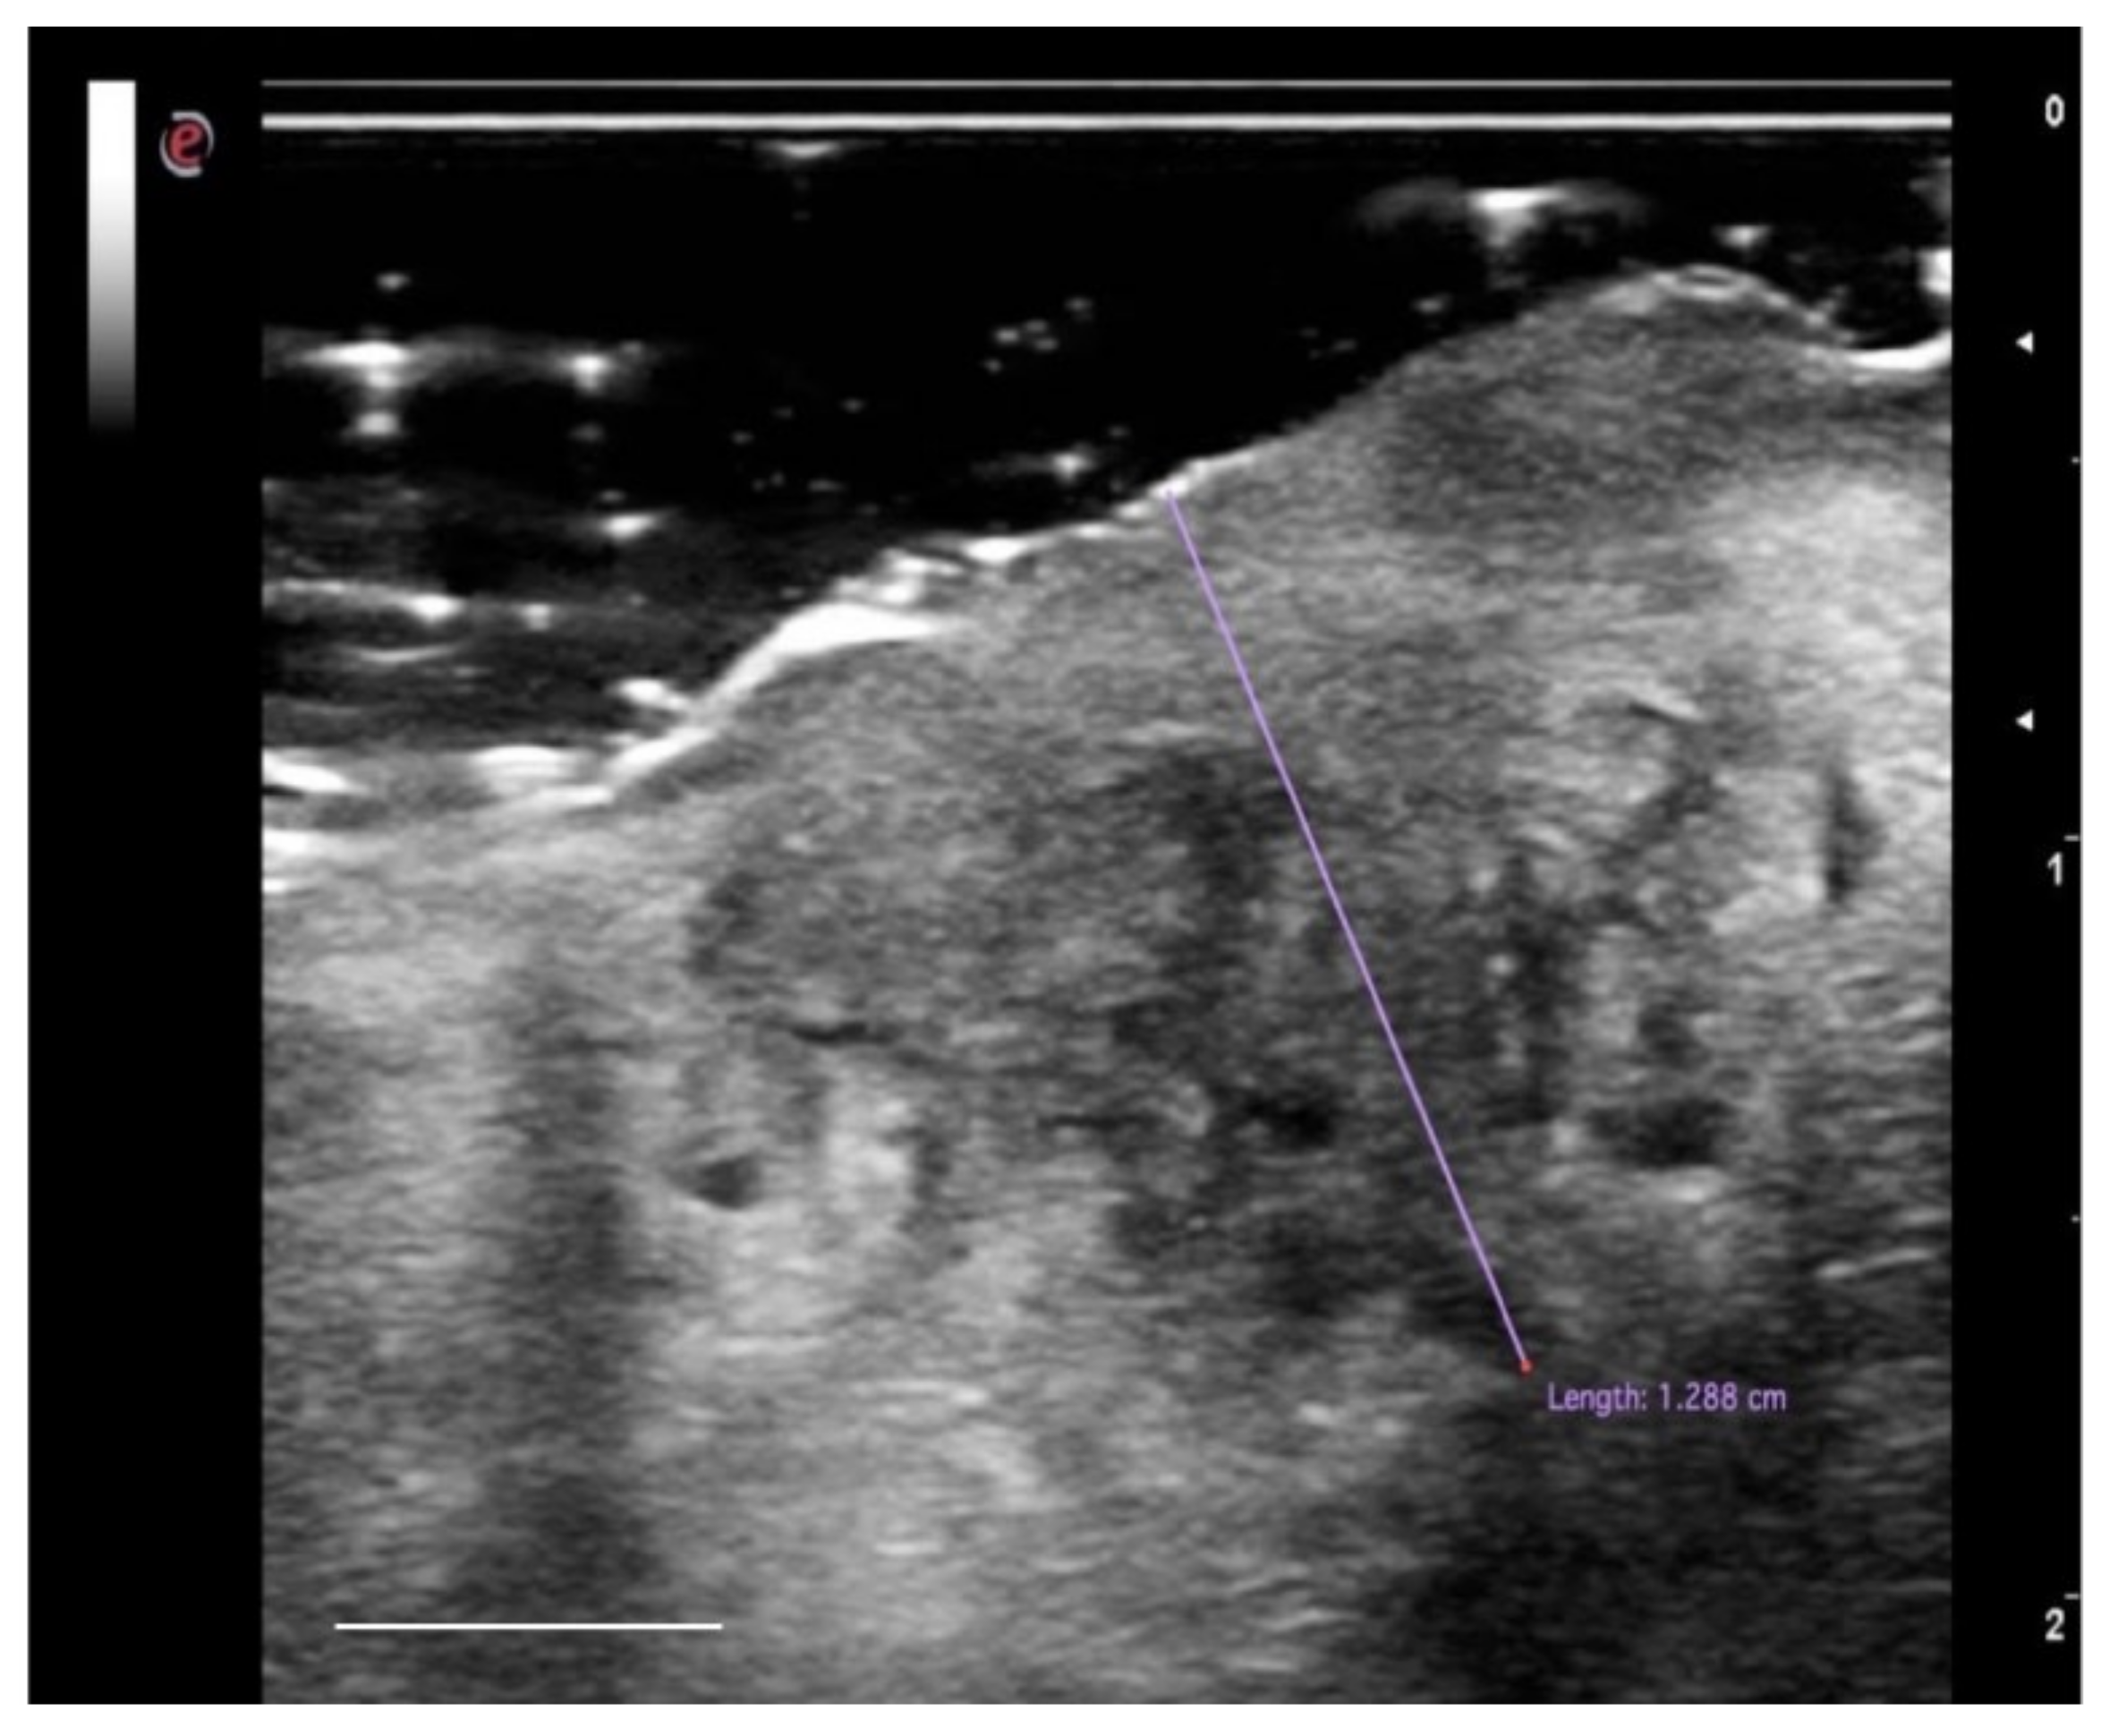

Intraoral ultrasound examination has the advantage of having direct contact with the region of interest, maintaining the characteristics of noninvasiveness, rapidity in execution, and repeatability, increasing the methods of possible applications [76]. Ultrasound techniques are considered particularly useful in determining the interface between tumor tissue and the surrounding myo-architecture [77,78]. A significant correlation has been reported between the histological aspects of the sample and the ultrasound image. OSCC appears as a rather defined hypoechoic lesion [76,79]. In other works [80,81], OSCC lesions were reported as hypoechoic with irregular margins and, in most cases, not well defined (Figure 5). Natori et al. reported that tumors with more invasive characteristics may show irregular and unclear margins on the ultrasound image [78].

The first intraoral application of ultrasound for OSCC imaging was initially described by Shintani et al. in 1997. This study aimed to evaluate and measure the extent of tumor thickness (TT), comparing it with the pathological sections and reporting a good agreement between the two techniques (R = 0.985). In a subsequent study [76], Shintani and colleagues compared the measurements of TT obtained with the ultrasound examination not only with the histology but also with computed tomography (CT) and magnetic resonance imaging (MRI). This study showed that intraoral ultrasound was more accurate in detecting and measuring tumors of the oral mucosa (R = 0.988), compared to CT (R = 0.976) and MRI (R = 0.911). Other studies [82] confirmed the capabilities of the US imaging technique in detecting lesions smaller than 1 mm thick (with a very high agreement with the histological examination), or at least lesions of about 1 mm of thickness were detectable in the intraoral ultrasound image in the context of the tongue parenchyma [78]. In this way [83], the ultrasound examination proved to be more accurate than MRI in measuring the TT. Accuracy increases in T1 and T2 tumors; for advanced-stage tumors (classification T3-T4), the determination of the thickness of the tumor in ultrasonography will be less accurate.

However, as the TT considers the entire extent of the tumor from the surface to the point of deepest invasion, this measure may underestimate the potential invasiveness in ulcerated forms (mainly in the tongue and floor of the mouth SCC) and overestimate the aggressiveness of the exophytic neoplasia limited within the epithelial layers. For these reasons, in 2018, the American Joint Committee on Cancer Union for International Cancer Control (AJCC-UICC) introduced another feature to be considered in the process of OSCC tumor staging: the depth of invasion (DOI) of the tumor [84]. DOI considers the subepithelial extent of the carcinoma because it measures, in millimeters, the distance from the basement membrane of the epithelial surface to the deepest point of tumor invasion and has proven to be a more reliable prognostic factor than the thickness of OSCC for predicting regional node involvement and the survival of patients with OSCC [85]. Despite both TT and DOI being routinely histologically measured after surgical procedures, the recent literature has reported the possibility of evaluating the DOI preoperatively, through high-frequency US, with a sensitivity and specificity of 91–93.1% and 100%, respectively, to assess the infiltration of the tumor beyond the lamina propria into the submucosa compared with histological measurements [73,86].

In conclusion, US imaging is an in vivo, noninvasive, and real-time diagnostic method that allows an accurate measurement of the tissues of the oral mucosa, and it can also be useful as a surgical aid. The value of this imaging technique appears to be superior, in terms of dimensional measurement, to techniques such as CT and MRI, in lesions with a thickness ≤5 mm. However, this instrument is operator-dependent and the learning curve is still very high.